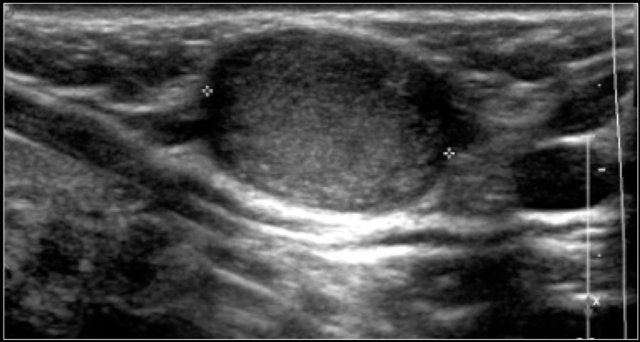

The images are of a fourteen-year-old boy with a painless swelling in the left neck.

The ultrasound shows several enlarged hypoechoic lymhnodes, that lack an hyper-echoic hilum.

Here another fourteen-year-old boy with a painless swelling in the left neck.

Ultrasound showed several enlarged lymhnodes.